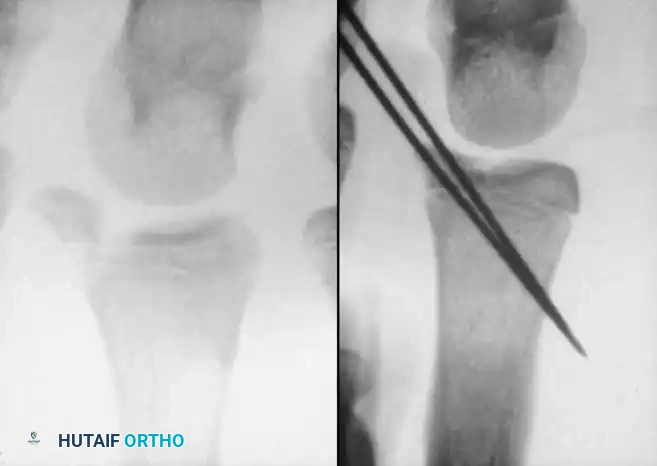

The thumb metacarpal is unique; its primary physis is located at the base, unlike the other metacarpals where the physis is at the head. (Rarely, a pseudo-epiphysis may be present at the distal end).

Image

However, pediatric Bennett fractures do occur and represent Salter-Harris type III intraarticular injuries.

A Bennett fracture in a child, much like a gamekeeper's thumb equivalent, involves the avulsion of the volar ulnar base by the anterior oblique ligament. If left displaced, it will result in joint incongruity and a high risk of a bony physeal bridge. Closed reduction and percutaneous pinning (CRPP) or ORIF with smooth pins is mandatory.

In older children nearing skeletal maturity, a fracture of the base of the first metacarpal that does not involve the physis (a Rolando-type fracture) can occur.

These Y- or T-shaped intraarticular fractures can often be satisfactorily reduced with longitudinal traction and percutaneously pinned under image intensification.